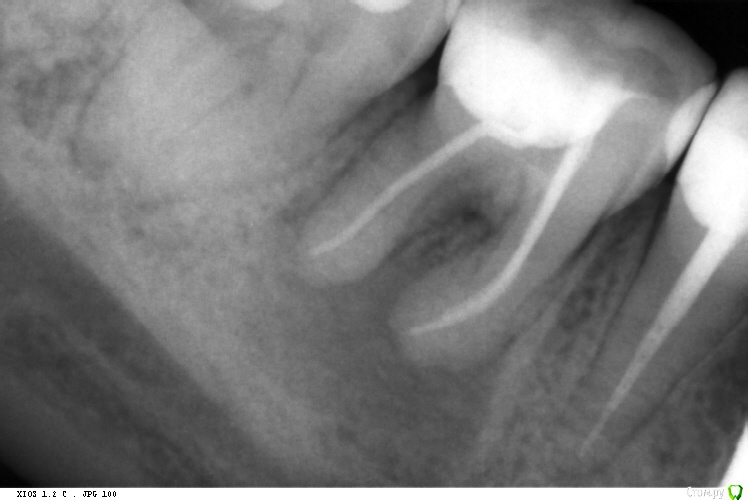

Shamxal Опубликовано 30 сентября, 2015 Поделиться Опубликовано 30 сентября, 2015 С вашего позволения хочу выставить рентген и задать пару вопросов Уважаемые коллеги, вопрос такой. Пришла пациентка с хроническим периапикальным разряжением. 46 зуб отрицательная реакция на перкуссию. Коффер снял, никак не получался снимок с клампом. Протокол иррегации 3 раза гипохлорит + озвучка, эдта и снова гипохлорит. Кроун даун дорожка затем протейперы. Апекслокатор в наличии. А тепер вопросы: 1) есть ли дополнительный 5 канал?2) если даже есть перфа в трифуркации, то в него невозможно попасть.3) прогноз лечения Ссылка на комментарий

DOCTORARSEN Опубликовано 30 сентября, 2015 Поделиться Опубликовано 30 сентября, 2015 С вашего позволения хочу выставить рентген и задать пару вопросов Уважаемые коллеги, вопрос такой. Пришла пациентка с хроническим периапикальным разряжением. 46 зуб отрицательная реакция на перкуссию. Коффер снял, никак не получался снимок с клампом. Протокол иррегации 3 раза гипохлорит + озвучка, эдта и снова гипохлорит. Кроун даун дорожка затем протейперы. Апекслокатор в наличии. А тепер вопросы: 1) есть ли дополнительный 5 канал?2) если даже есть перфа в трифуркации, то в него невозможно попасть.3) прогноз лечения по мне, зуб на удаление Ссылка на комментарий